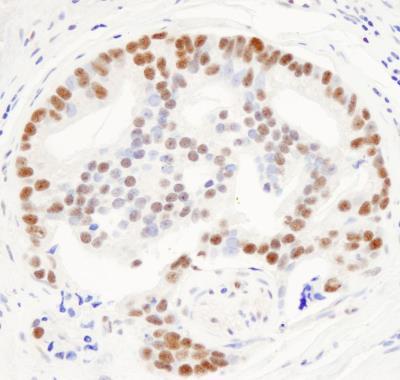

Supportive validation

- Submitted by

- Novus Biologicals (provider)

- Main image

- Experimental details

- Immunohistochemistry-Paraffin: THRAP3 Antibody [NB100-40848] - Sample: FFPE section of human prostate carcinoma. Antibody: Affinity purified rabbit anti- THRAP3/TRAP150 used at a dilution of 1:1,000 (0.2ug/ml). Detection: DAB